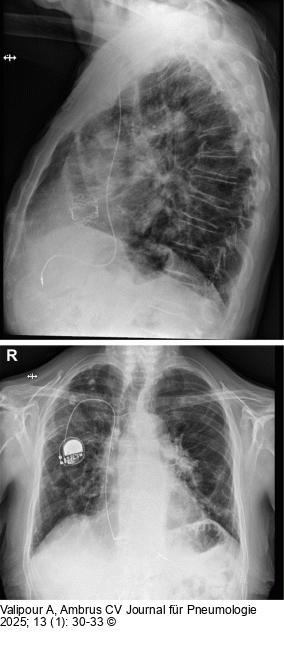

Abbildung 3: Thorax-Röntgen

Thorax-Röntgen